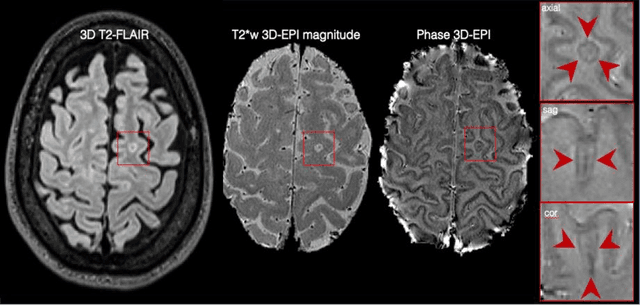

Abstract:The current multiple sclerosis (MS) diagnostic criteria lack specificity, and this may lead to misdiagnosis, which remains an issue in present-day clinical practice. In addition, conventional biomarkers only moderately correlate with MS disease progression. Recently, advanced MS lesional imaging biomarkers such as cortical lesions (CL), the central vein sign (CVS), and paramagnetic rim lesions (PRL), visible in specialized magnetic resonance imaging (MRI) sequences, have shown higher specificity in differential diagnosis. Moreover, studies have shown that CL and PRL are potential prognostic biomarkers, the former correlating with cognitive impairments and the latter with early disability progression. As machine learning-based methods have achieved extraordinary performance in the assessment of conventional imaging biomarkers, such as white matter lesion segmentation, several automated or semi-automated methods have been proposed for CL, CVS, and PRL as well. In the present review, we first introduce these advanced MS imaging biomarkers and their imaging methods. Subsequently, we describe the corresponding machine learning-based methods that were used to tackle these clinical questions, putting them into context with respect to the challenges they are still facing, including non-standardized MRI protocols, limited datasets, and moderate inter-rater variability. We conclude by presenting the current limitations that prevent their broader deployment and suggesting future research directions.